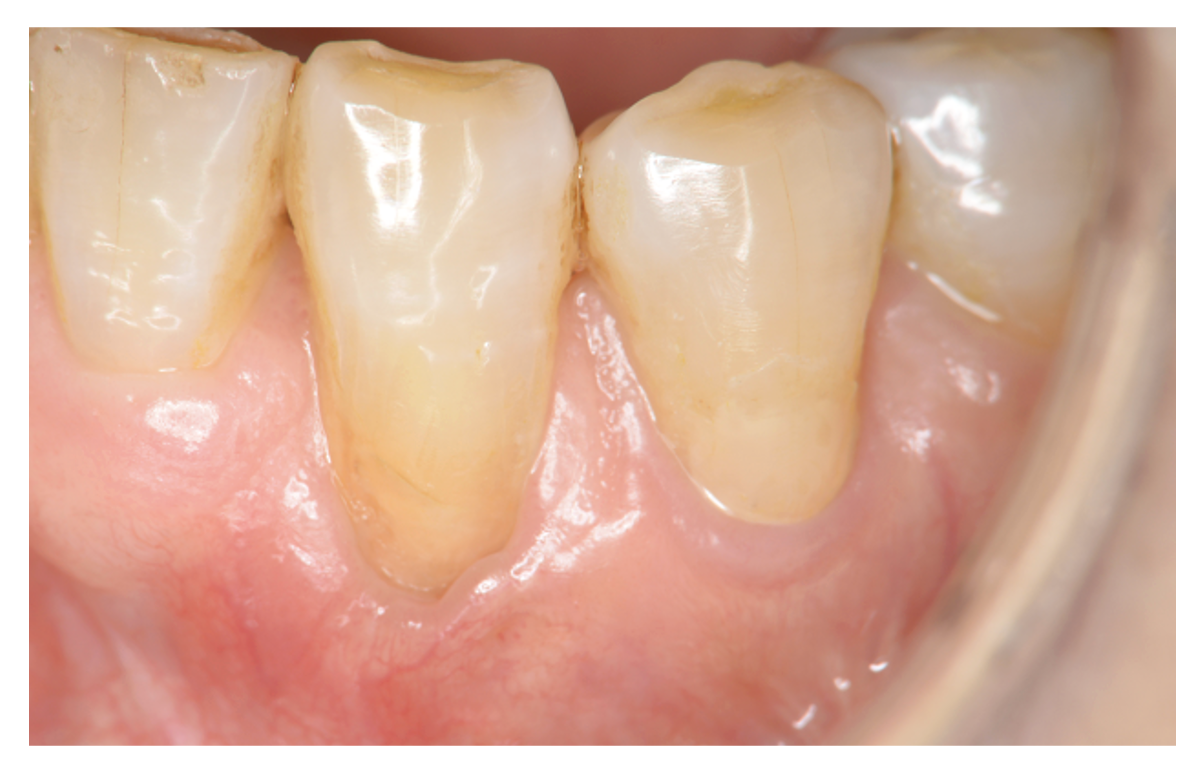

下がった歯茎を元通りにしたい

術前

術後5年

| 主訴 | 歯茎が下がってきている。 歯磨きもしにくいし、見た目も気になる。 このまま下がって歯が抜けないか心配。 |

| 治療内容 | ブラッシング指導、歯石の除去 歯周形成手術(結合組織移植術) →歯茎の再生手術 |

| 治療期間 | 2ヶ月 術後3ヶ月経過してメインテナンスに移行 |

| 費用 | 77,000 *対象歯の本数により異なります。 |

| リスク・副作用 | 手術部位が2箇所になります。移植片を採取する部位(上あごの歯肉)と移植する部位(歯肉退縮部位)。特に採取部位では疼痛や出血を伴います。また、退縮量が大きい場合や症例によっては2度に分けて手術を行う場合があります。 |